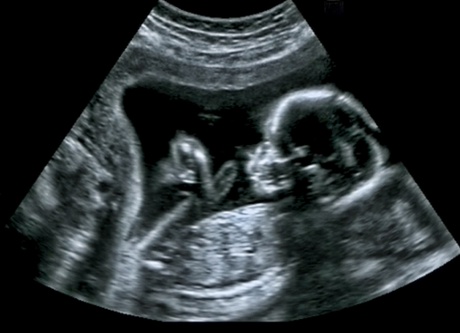

The University of Aberdeen is among nine UK universities selected to make up the new NIHR Challenge Maternity Disparities Consortium with the aim of tackling inequalities in maternity care.

The research carried out by the consortium will focus on inequalities before, during and after pregnancy.